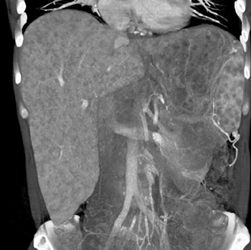

Sarcoidosis